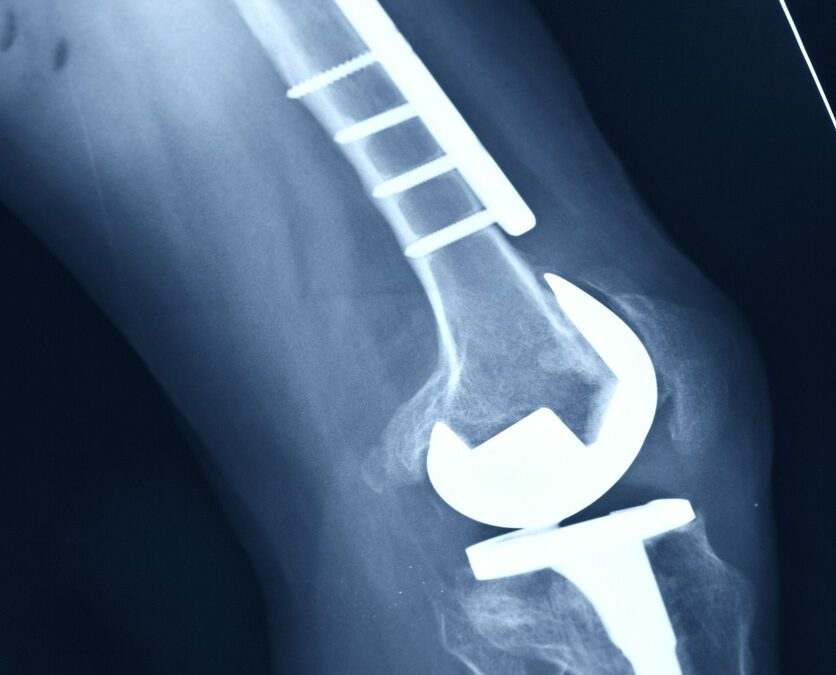

Osteotomia to zabieg chirurgiczny polegający na przecięciu kości w celu korekcji jej kształtu lub położenia. Stosuje się go głównie w ortopedii do leczenia schorzeń narządu ruchu, takich jak deformacje stawów czy choroby zwyrodnieniowe. Celem tego zabiegu jest...